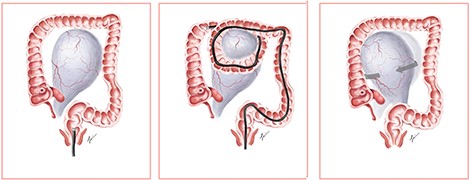

We propose a postulated mechanism of ovarian torsion in this patient (Fig. 3). Due to the large size of the ovarian mass, looping during colonoscopy could have caught the ovarian mass between the bowels, leading to the twisting of the mass on its pedicle by the looped segment of the bowel. Application of abdominal compression to advance the endoscope could have precipitated further twisting of the mass, resulting in ovarian torsion. Although causality between colonoscopy and ovarian torsion cannot be proven, the development of acute abdominal pain shortly after colonoscopy prompts us to consider that the colonoscope could have mechanically twisted the ovary on its pedicle.